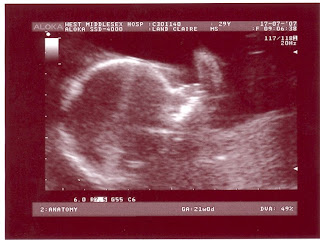

Here are some of the photos. Once again they never do the scan justice. I just wish we could get a copy of the screen in video it is some much more detailed.

An overview shot. Crown to Rump was 17cm.